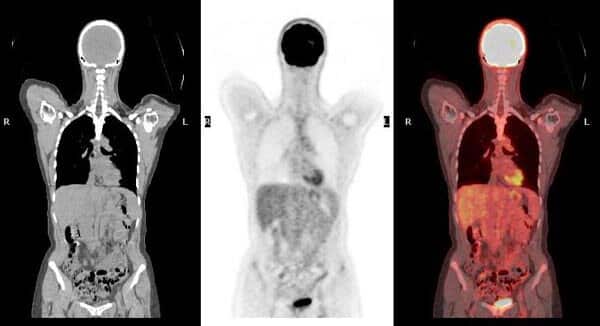

An 18F-Choline PET/CT scan combines functional PET imaging with anatomical CT imaging. It uses a choline-based radiotracer labelled with Fluorine-18, which highlights areas of abnormal cellular activity.

Because rapidly dividing cancer cells and overactive parathyroid tissue require increased cell membrane synthesis, they absorb more choline. As a result, these areas become clearly visible on PET-CT images, allowing accurate identification of disease location and extent.

Subsequently, the PET scanner detects tracer uptake, while the CT component provides precise anatomical detail. Together, these images create a three-dimensional view of abnormal tissue, enabling accurate localisation and assessment.